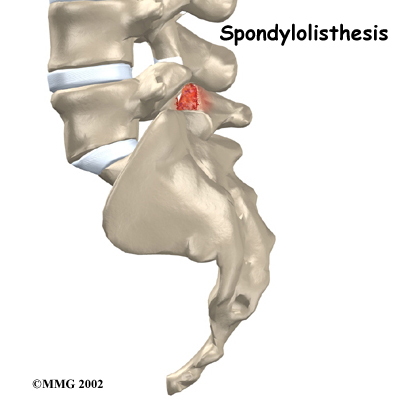

Normally, the bones of the spine (the vertebrae) stand neatly stacked on top of one another. Ligaments and joints support the spine. Spondylolisthesis alters the alignment of the spine. In this condition, one of the spine bones slips forward over the one below it. As the bone slips forward, the nearby tissues and nerves may become irritated and painful.

Spondylolisthesis may very rarely be congenital, which means it is present at birth. It can also occur in childhood as a result of injury. In older adults, degeneration of the disc and facet (spinal) joints can lead to spondylolisthesis.

Spondylolisthesis from degeneration usually affects people over 50 years old. This condition occurs in African Americans more often than in whites. Women are affected more often than men. The effect of the female hormone estrogen on ligaments and joints is to cause laxity or looseness. The higher levels of estrogen in women may account for the greater incidence of spondylolisthesis. Degenerative spondylolisthesis mainly involves slippage of L4 over L5.

In younger patients (under 20 years old), spondylolisthesis usually involves slippage of the fifth lumbar vertebra over the top of the sacrum. There are several reasons for this. First, the connection of L5 and the sacrum forms an angle that is tilted slightly forward, mainly because the top of the sacrum slopes forward. Second, the slight inward curve of the lumbar spine creates an additional forward tilt where L5 meets the sacrum. Finally, gravity attempts to pull L5 in a forward direction.

Facet joints are small joints that connect the back of the spine together. Normally, the facet joints connecting L5 to the sacrum create a solid buttress to prevent L5 from slipping over the top of the sacrum. However, when problems exist in the disc, facet joints, or bony ring of L5, the buttress becomes ineffective. As a result, the L5 vertebra can slip forward over the top of the sacrum.

A condition called spondylolysis can lead to the slippage that happens with spondylolisthesis. Spondylolysis is a defect in the bony ring of the spinal column. It affects the pars interarticularis, mentioned earlier. This defect is most commonly thought to be a stress fracture that happens from repeated strains on the bony ring. Participants in gymnastics and football commonly suffer these strains. Spondylolysis can lead to the spine slippage when a fracture occurs on both sides of the bony ring. This slippage is called spondylolisthesis. The slippage is from I through IV, one being mild, IV often causing neurological symptoms. The back section of the bony ring separates from the main vertebral body, so the injured vertebra is no longer connected by bone to the one below it. In this situation, the facet joints can't provide their normal support. The vertebra on top is then free to slip forward over the one below.

Degenerative changes in the spine (those from wear and tear) can also lead to spondylolisthesis. The spine ages and wears over time, much like hair turns gray. These changes affect the structures that normally support healthy spine alignment. Degeneration in the disc and facet joints of a spinal segment causes the vertebrae to move more than they should. The segment becomes loose, and the added movement takes an additional toll on the structures of the spine. The disc weakens, pressing the facet joints together. Eventually, the support from the facet joints becomes ineffective, and the top vertebra slides forward.

An ache in the low back and buttock areas is the most common complaint in patients with spondylolisthesis. Pain is usually worse when standing, walking, or bending backward and may be eased by resting or bending the spine forward. Leaning on a counter top, piece of furniture, or shopping cart are common ways to alleviate (reduce) the symptoms.

Slippage can also cause nerve compression. Nerve compression is a result of . As the spine slips forward, the nerves may be squeezed where they exit the spine. This condition also reduces space in the spinal canal where the vertebra has slipped. This can put extra pressure on the nerve tissues inside the canal. Nerve compression can cause symptoms where the nerve travels and may include numbness, tingling, slowed reflexes, and muscle weakness in the legs.